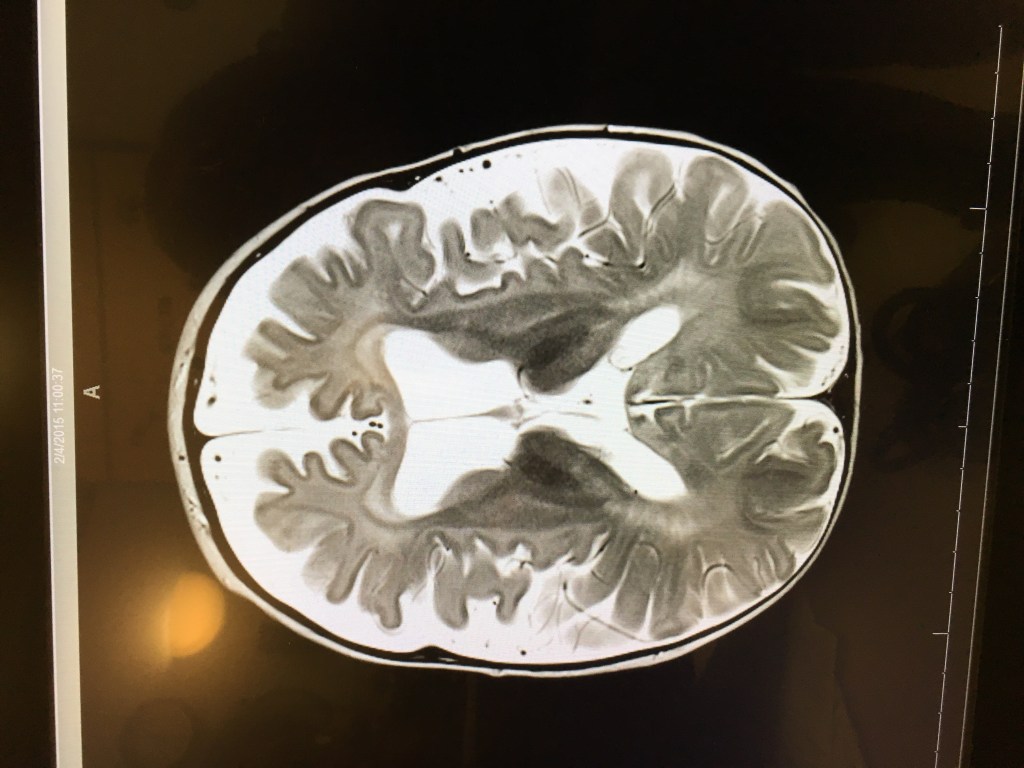

We didn’t see the images of the MRI (or learn in detail about what they saw) until February 6th, but I want to include them in this post.

We have never shared these publicly.

Here are two screenshots of Tori’s brain on February 4, 2015.

We knew then that something was seriously wrong, even from our medically-untrained perspective.

Tori will have another MRI later this month and I will be very interested to compare the images to see the disease progression.